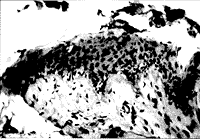

病理组织学检查所见证实囊壁为非角化复层鳞状上皮含有杯状细胞(图4)。在上皮表面发现了表示变性的脱落上皮细胞的蛋白质性质物质。囊壁含有毛干、皮脂腺和炎性细胞(图5)。所有的切片均与起源于结膜的皮样囊肿诊断相符。

图5 囊壁含有毛干、皮脂腺和炎性细胞